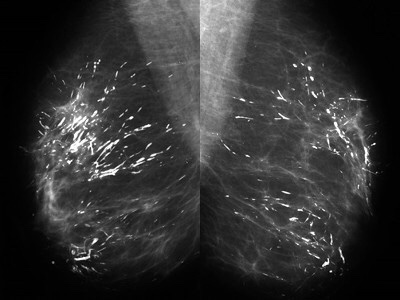

👉When coarse rod-like ductal calcifications are diffuse, bilateral, and not confined to a single lobe, they can be confidently assumed to result from plasma cell mastitis, and they do not require further evaluation or biopsy.

👉The process is called secretory disease because there is a stagnant, viscous fluid that eventually petrifies and results in the smooth contoured calcifications.

👉Some of them are branching and look like malignant casting type calcifications, but the key distinguishing feature is the diffuse, multilobe, bilateral nature of the process.